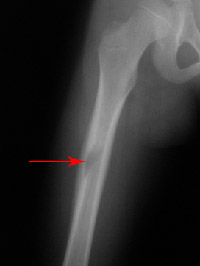

Your doctor will probably obtain X-rays for further information. Each type of tumor can exhibit different characteristics on X-ray. Some dissolve bone or make a hole in the bone. Some cause an extra formation of bone. Some can result in a mixture of these findings. In other cases, it may be difficult to tell what kind of tumor is involved, and additional imaging studies such as MRI (magnetic resonance imaging) or CT (computed tomography) could be called for.